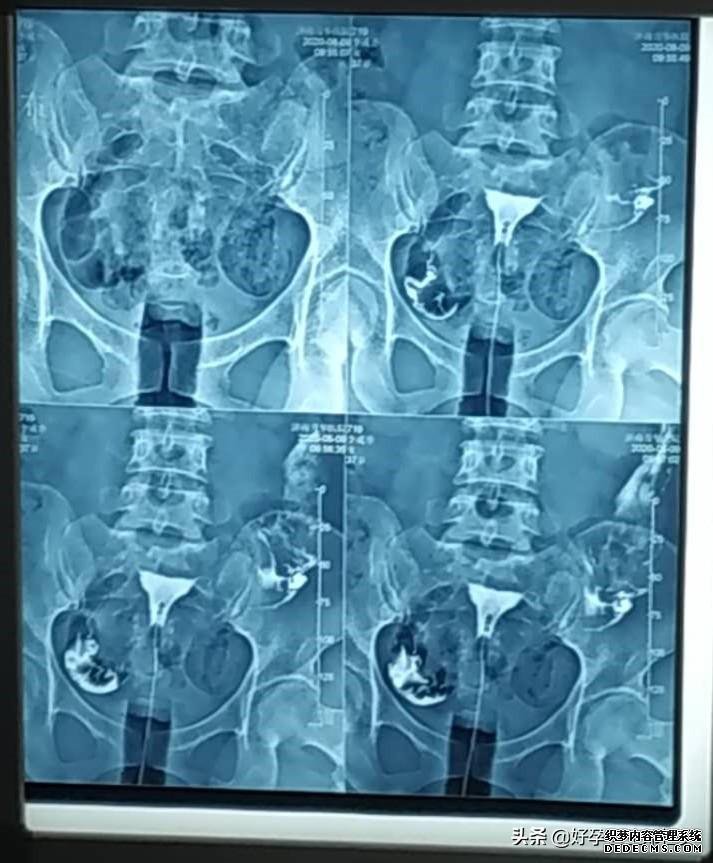

输卵管复查后,我开始教李姐怎么测排卵算准排卵日安排同房,把受孕几率提到最高,这样才坚持了三个月,李姐就如愿怀孕了,昨天去查了血(查血报告见上方图一,下面是试纸图),各方面值都非常好,这下李姐总算是放心了!

子宫输卵管造影是通过导管向子宫和输卵管注入造影剂,通过X线来透视和摄片,然后根据造影剂在输卵管和盆腔内的造影情况分析输卵管通畅程度、阻塞的部位和宫腔的情况,是临床上很多不孕症女性常做的检查之一。

正常的子宫输卵管造影,应该是很容易就能把造影剂推进去,而且患者不会出现疼痛等明显症状。现在临床上的造影剂选用的都是碘水,常用76%的泛影葡胺,渗透压低,粘稠度低,可以扩散到输卵管的分泌物中,15分钟就能完成摄片,减少X线照射时间,注入半小时以内就能被身体吸收,对女性身体伤害小。